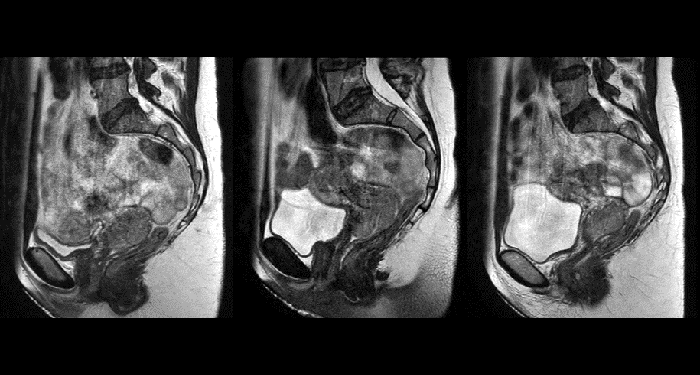

With its exceptional soft-tissue visualization capabilities and wide range of image contrasts, MRI has become a powerful tool to help more precisely define tumor boundaries. This is particularly important as it has been established that there is a high degree of uncertainty in target volume delineation, and it is even reported to represent the largest uncertainty in the entire radiotherapy process for most tumor sites**. Better visualization of the target area and nearby organs-at-risk is a key factor in enhancing target volume delineation. MRI’s expanding role also can be attributed to its functional imaging capabilities, which can inform both target characterization and treatment response.

Ingenia MR-RT is a dedicated MR simulation platform that provides high quality, high contrast MR images acquired with the patient in treatment position. Designed for the needs of radiation oncology, this comprehensive solution provides the tools and software needed for versatile and efficient imaging for radiotherapy planning.

MR-linac simulation package for Elekta Unity

The Philips Ingenia MR-RT simulation platform with MR linac simulation package is an ideal complement to Elekta Unity. With consistent workflows and image quality from MR simulation through to online MR guidance during radiation treatment, it will let you exploit the many similarities and synergies between Philips Ingenia MR-RT and Elekta Unity.